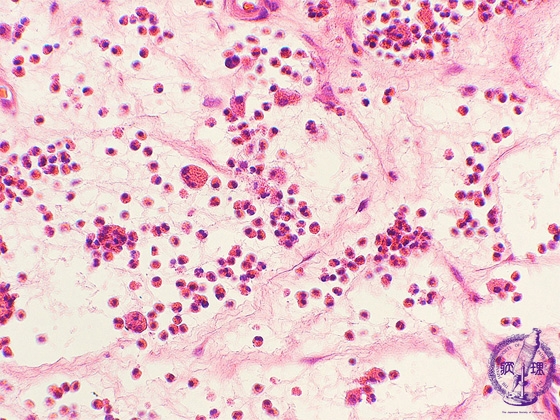

Microscopic view (high power view): Inflammatory cells are predominantly composed of eosinophils, and marked stromal edema is observed.